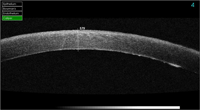

Figura 3 y

Figura 4, fase infecciosa de una queratitis estromal en la interfase y posterior resolución) y desprendimientos de la membrana Descemet, entre otras muchas patologías.

Figura 4. Resolución de la infección con aposicionamiento del flap.